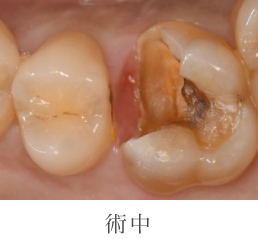

むし歯治療の詳細

- 主訴

- 他院で金属か自費を勧められたが、保険で白い歯にしたい(当院へのセカンドオピニオンで受診)

- 治療期間

- 1週間

- 治療内容

- 虫歯の除去 印象 CAD/CAM Inセット

- 治療のリスク

- 術後しみる可能性があります

- 治療費

- 保険診療に準ずる